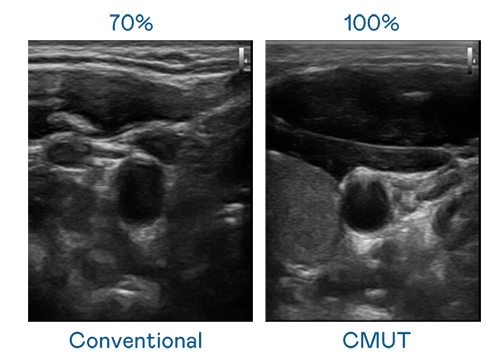

申博太陽城運用 TFT 陣列 (Array) 制程延伸尖端感測技術(shù) ,開發(fā)出多種感測元件的產(chǎn)品。高解析度、品質(zhì)穩(wěn)定且可量產(chǎn)的 CMUT 元件,可制作高解析度超音波探頭、貼片型探頭 ,對病患實施精準(zhǔn)檢測與長時間生理監(jiān)測 。為滿足 X光設(shè)備輕量化、可移動 ,甚至需針對待測物進(jìn)行外觀客制化的新需求 ,申博太陽城結(jié)合非晶矽 (a-Si) 制程與新的封裝技術(shù),實現(xiàn)可撓曲、具優(yōu)異 TFT 遷移率 (mobility) 的柔性 X光感測器。目前也已提供完整玻璃和曲面型 X光感測器檢測解決方案 。